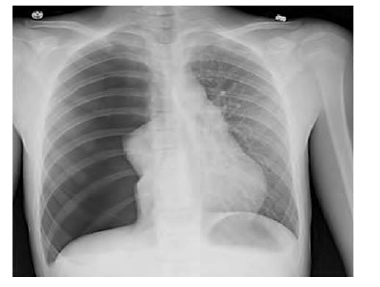

Após sofrer trauma de tórax contuso, determinado paciente de 35 anos de idade chega à emergência e relata que é motorista de moto e colidiu contra um carro, com cinemática grave. Durante a avaliação inicial, o paciente encontra-se alerta, conversando, lúcido. A via aérea está prévia, ausculta pulmonar com murmúrio abolido à direita, expansão torácica assimétrica, sem sinais de choque ou instabilidade hemodinâmica, sem turgência jugular. Ele apresenta abdome flácido e indolor, pelve estável, sem outras alterações no exame físico. Os raios X de tórax a seguir foram realizados na admissão do paciente em unidade hospitalar.

Com base nesse caso clínico hipotético e na imagem radiográfica apresentada, e considerando os conhecimentos médicos correlatos, assinale a alternativa correta.

A imagem indica um pneumotórax à direita, e a conduta adequada é drenagem pleural direita.